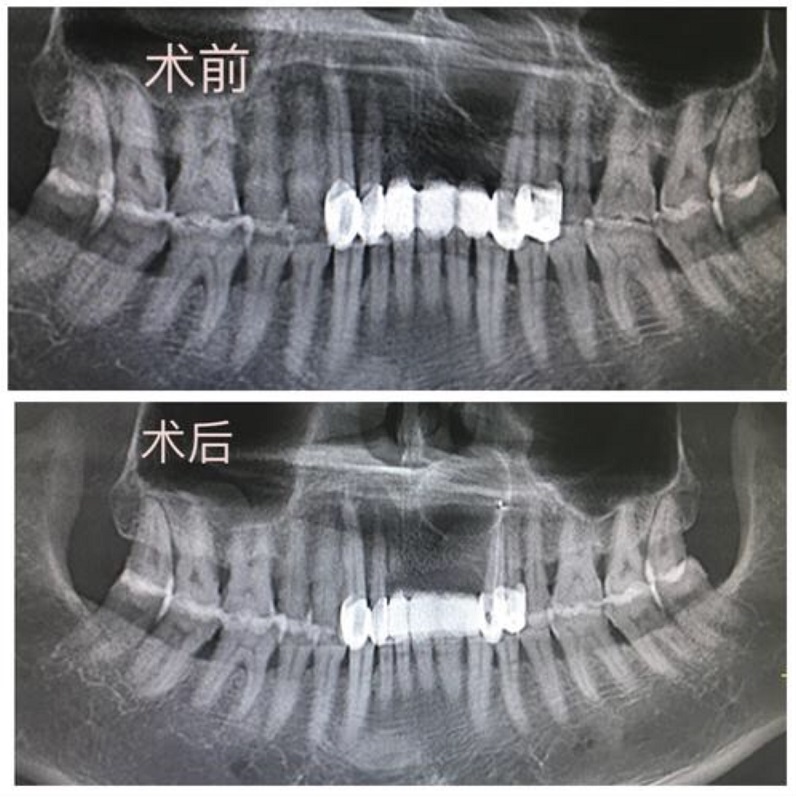

術(shù)前術(shù)后曲面斷層片對(duì)照